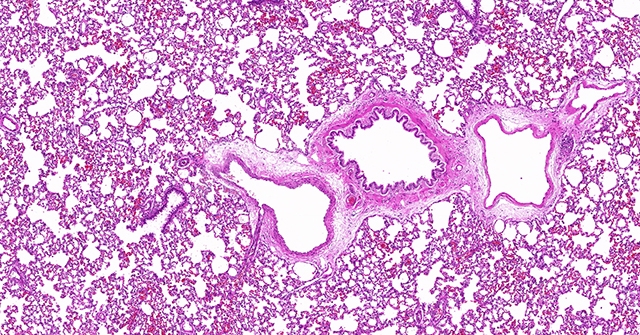

染色是一种常见的化学实验技术,用于在生物学研究、医学诊断、组织学研究等领域中显示和区分细胞或组织的结构和成分。其中,常用的一种染色方法是使用可溶于水的染料将细胞或组织中的特定结构染色,从而使其能够被显微镜观察和分析。在这个过程中,一种被广泛使用的染料就是“HE染料”。

“HE染料”的全称是“Hematoxylin and Eosin”,即“血红木素和苏木精”。它由两种染料组成,分别是“hematoxylin”和“eosin”。这两种染料有着不同的性质和作用,在染色过程中发挥着重要的作用。

“hematoxylin”,它是从血红木树皮中提取得到的天然染料。它具有亲和力强、专一性好的特点,对细胞核和酸性成分具有较强的亲和力。在染色过程中,hematoxylin能够与细胞核内的DNA结合,使其呈现出蓝色或紫色的颜色。这使得我们能够清晰地观察到细胞核的形态、数量和位置,从而进行细胞结构和组织构成的分析。

“eosin”则是一种酸性染料,它具有亲和力强、颜色鲜艳的特点。在染色过程中,eosin能够与细胞内的碱性成分结合,使其呈现出红色或橙色的颜色。这样,我们可以通过eosin染色来显示细胞质、细胞间质和胶原纤维等碱性成分,从而更全面地了解细胞和组织的结构和组成。

“HE染料”的使用它可以帮助我们清晰地观察和区分细胞核和胞质等细胞结构,为研究细胞功能和病理变化提供了基础。其次,通过HE染色,我们能够获得组织的整体结构和组成信息,了解组织的功能和病理变化,从而为医学诊断和疾病研究提供了重要依据。此外,HE染色也被广泛应用于药物筛选、生物工程等领域,帮助科学家们更好地了解和探索生物体的奥秘。它的使用不仅加深了我们对生物体的认识,还为各个领域的研究提供了强有力的工具和手段。